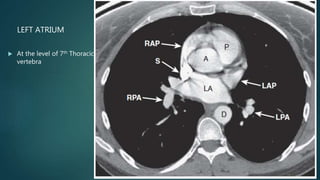

LEFT ATRIUM

 At the level of 7th Thoracic

vertebra